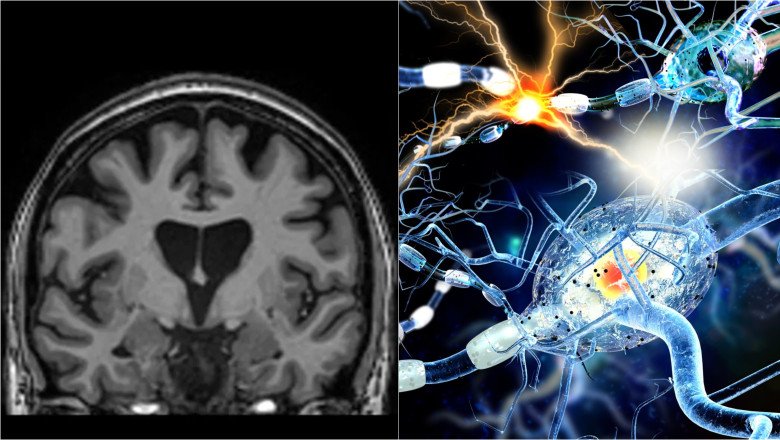

Cercetarea a fost realizată de o echipă de la Universitatea Griffith, în cadrul Centrului Naţional pentru Neuroimunologie şi Boli Emergente (NCNED), şi a folosit tehnici avansate de rezonanţă magnetică (RMN) pentru a evalua sănătatea creierului la persoane care avuseseră Covid-19. Rezultatele au fost comparate cu cele ale unor participanţi care nu au fost infectaţi cu virusul.

Analiza imaginilor RMN a arătat semne clare că o infecţie anterioară cu SARS-CoV-2 poate lăsa urme detectabile în creier, inclusiv atunci când participanţii nu raportau simptome persistente.

Echipa a utilizat imagistică multimodală pentru a examina atât substanţa cenuşie, cât şi substanţa albă, regiuni esenţiale pentru memorie, funcţii cognitive şi sănătatea generală a creierului.

Autorul principal al studiului, dr. Kiran Thapaliya, a declarat că investigaţiile RMN au evidenţiat modificări importante ale substanţelor chimice din creier, ale intensităţii semnalului şi ale structurii ţesutului cerebral.